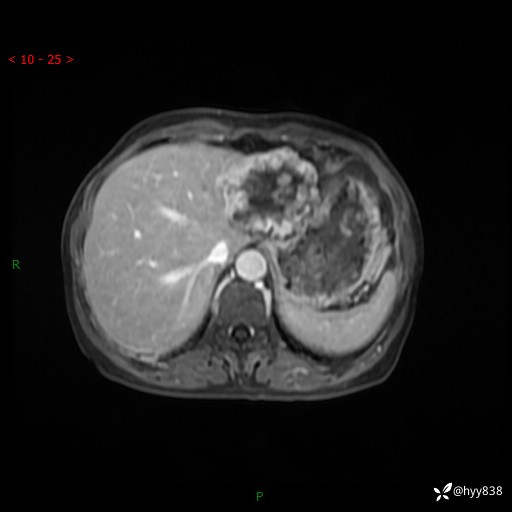

老年女性,偶然发现肝脏占位,综合各个序列,你考虑什么---结果公布

主诉:发现肝脏占位性病变2天

简要病史:患者2天前因“腰疼”至当地医院就诊时发现肝脏左叶占位性病变,无发热、畏寒,无皮肤黄染,无腹痛、腹泻,无恶心、呕吐、厌油等不适,今进一步诊治遂来我院就诊,门诊以“肝脏占位性病变性质待查”收入我科。 起病以来,患者精神、睡眠一般,饮食欠佳,二便正常,体力、体重无明显减轻,

辅助检查:MRI

临床诊断:肝占位

肝脏MRI平扫(同反相位)

T2WIfs+DWI

增强(动脉期+静脉期+延迟期)